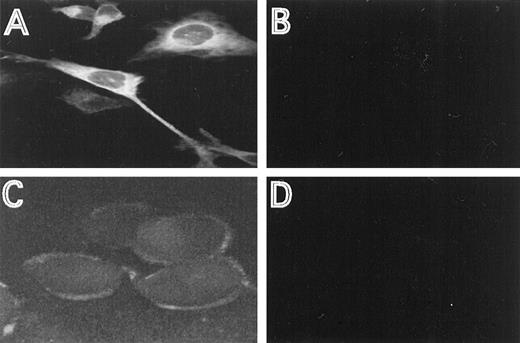

The cellular distribution of the induced HFE protein was analyzed by immunofluorescence, using HFE antisera directed against an N-terminal or C-terminal HFE peptide. In permeabilized cells, most of the staining occurred intracellular in a perinuclear location (Fig2A). This distribution is similar to the one described for the transferrin receptor.16 29 Using the antiserum directed against the N-terminal peptide, membrane staining was clearly detectable with nonpermeabilized cells, demonstrating that a distinct fraction of HFE is associated with the cell membrane (Fig2C). The specificity of the immunostaining experiments is demonstrated by the lack of fluorescence in cells repressed for HFE synthesis, under otherwise identical experimental conditions (Fig 2B and D).

Immunostaining of HFE. HtTA-HFE cells were grown on coverslips for 4 days in the absence (A,C) or presence (B,D) of 1 μg/mL doxycycline. Immunostaining was perfromed as described in the methods. Permeabilzed cells were incubated with the antiserum directed against the C-terminal peptide (A,B), unpermeabilized cells were incubated with the antiserum directed against the N-terminal peptide (C,D).